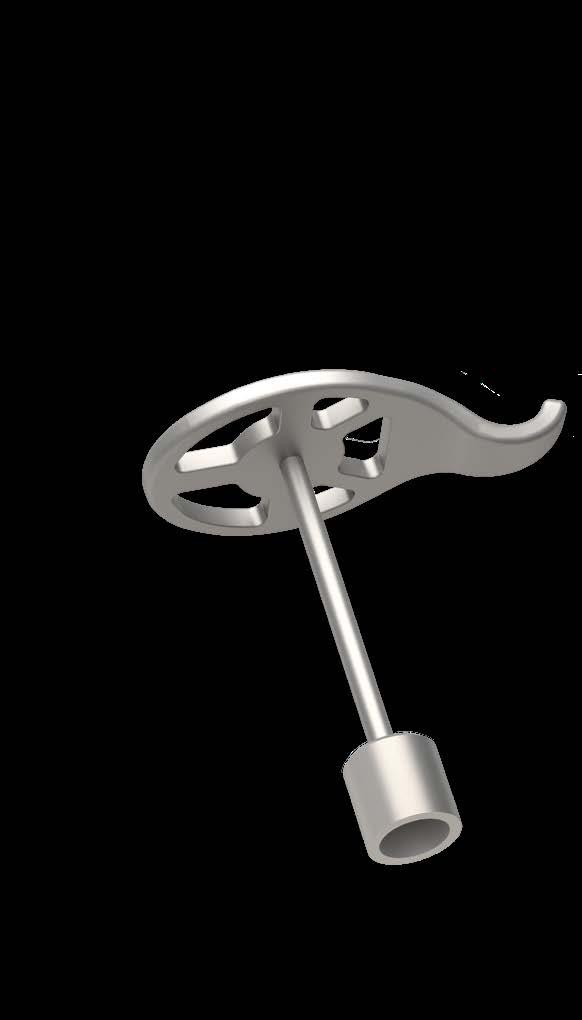

OMEGA CONNECTOR

OPTIMIZED FIT

In total ossicular reconstruction, movements of the tympanic membrane can alter the implant position on the stapes footplate. This risk may be reduced by using the OMEGA CONNECTOR together with a total prosthesis. The OMEGA CONNECTOR is designed to compensate for tympanic membrane movements and provide additional stability.

FLEXIBLE JOINT CONNECTION

With sufficient footplate access, the OMEGA CONNECTOR increases the medial surface contact of a total prosthesis. The micro ball joint connects with the cannulated stem of the KURZ total prosthesis. In this way it accommodates drum to head plate angles without prosthesis manipulations.

STABLE CONNECTION

An aspiration tip is ideally used to place the OMEGA CONNECTOR first into the middle ear. The cupped medial end of the total prosthesis is assembled with the OMEGA CONNECTOR in situ. A snug and stable fit between the two prostheses makes fixation with adhesive unnecessary. The undersurface of the shoe has a longitudinally milled recess to compensate for footplate irregularity.

Developed in close collaboration with Dr. med. G. Schmid, Reutlingen, Germany.

MODULAR SYSTEM FOR KURZ TOTAL PROSTHESES

The OMEGA CONNECTOR is compatible with all KURZ total prostheses that have a hollow stem with a diameter of 0.8 mm at the end of the shaft:

• TTP-VARIAC® System Total

• TTP®-Tuebingen AERIAL Total

• Duesseldorf AERIAL Total

• MNP Malleus Notch Total

• MunichLMU Total

QUICK DETERMINATION OF AVAILABLE SPACE

With the aid of the specially developed OMEGA CONNECTOR Sizer the surgeon can intraoperatively determine whether adequate space prevails for the OMEGA CONNECTOR between the stapes crura remnants. The measuring tip of the OMEGA CONNECTOR Sizer precisely corresponds to the dimensions of the OMEGA CONNECTOR.